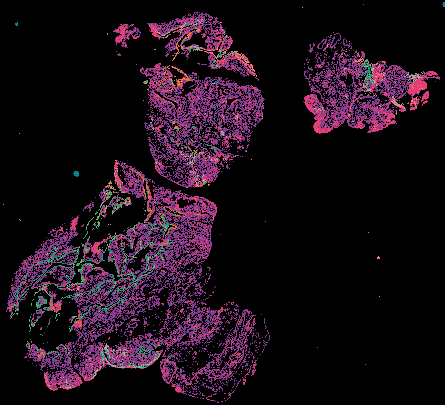

Ovarian STIC Spatial Transcriptomic Data from GeoMX and Multiplex Imaging

Ovarian Cancer with Annotation - LSP15327

Ovarian Cancer with Annotation - LSP15343